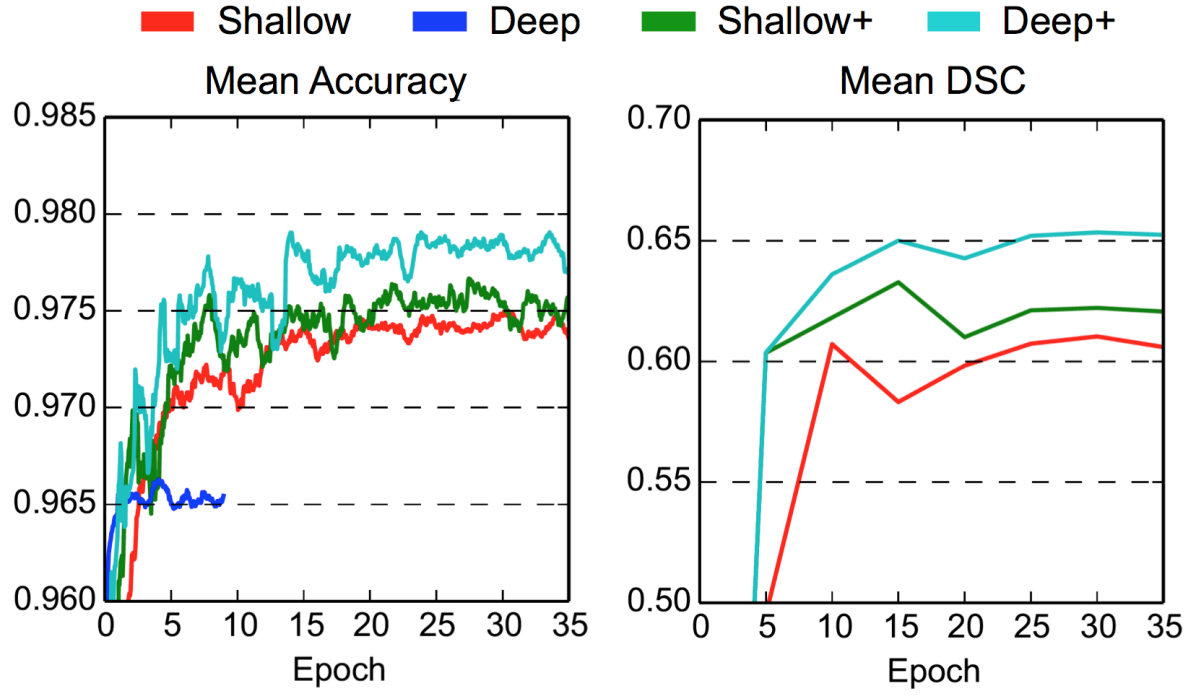

The 5-layers baseline CNN (Fig. 2), here referred to as the “Shallow” model, is extended to 9-layers by replacing each convolutional layer that uses kernels with two layers that use kernels (Fig. 4). This model is referred to as “Deep”. Training the latter, however, utterly fails with the model making only predictions corresponding to the background class. This problem is related to the challenge of preserving the signal as it propagates through deep networks and its variance gets multiplied with the variance of the weights, as previously discussed in Sec. 2.3. One of the causes is that the weights of both models have been initialized with the commonly used scheme of sampling from the normal distribution (cf. Krizhevsky et al. (2012)). In comparison, the initialization scheme by He et al. (2015), derived for preserving the signal in the initial stage of training, results in higher values and overcomes this problem. Further preservation of the signal is obtained by employing Batch Normalization. This results in an enhanced 9-layers model which we refer to as “Deep+”, and using the same enhancements on the Shallow model yields “Shallow+”. The significant performance improvement of Deep+ over Shallow+, as shown in Fig. 7, is the result of the greater representational power of the deeper network. The two models need similar computational times, which highlights the benefits of utilizing small kernels in the design of 3D CNNs. Although the deeper model requires more sequential (layer by layer) computations on the GPU, those are faster due to the smaller kernel size.

Figure 8 shows the improvement DeepMedic achieves over the single pathway model Deep+. In Fig. 9 we show two representative visual examples of this improvement when using the multi-scale CNN. Finally, we confirm that the performance increase can be accounted to the additional context and not the additional capacity of DeepMedic. To this end, we build a big single-scale model by doubling the FMs at each of the 9-layers of Deep+ and adding two hidden layers. This 11-layers deep and wide model, referred to as “BigDeep+”, has the same number of parameters as DeepMedic. The performance of the model is not improved, while showing signs of over-fitting.